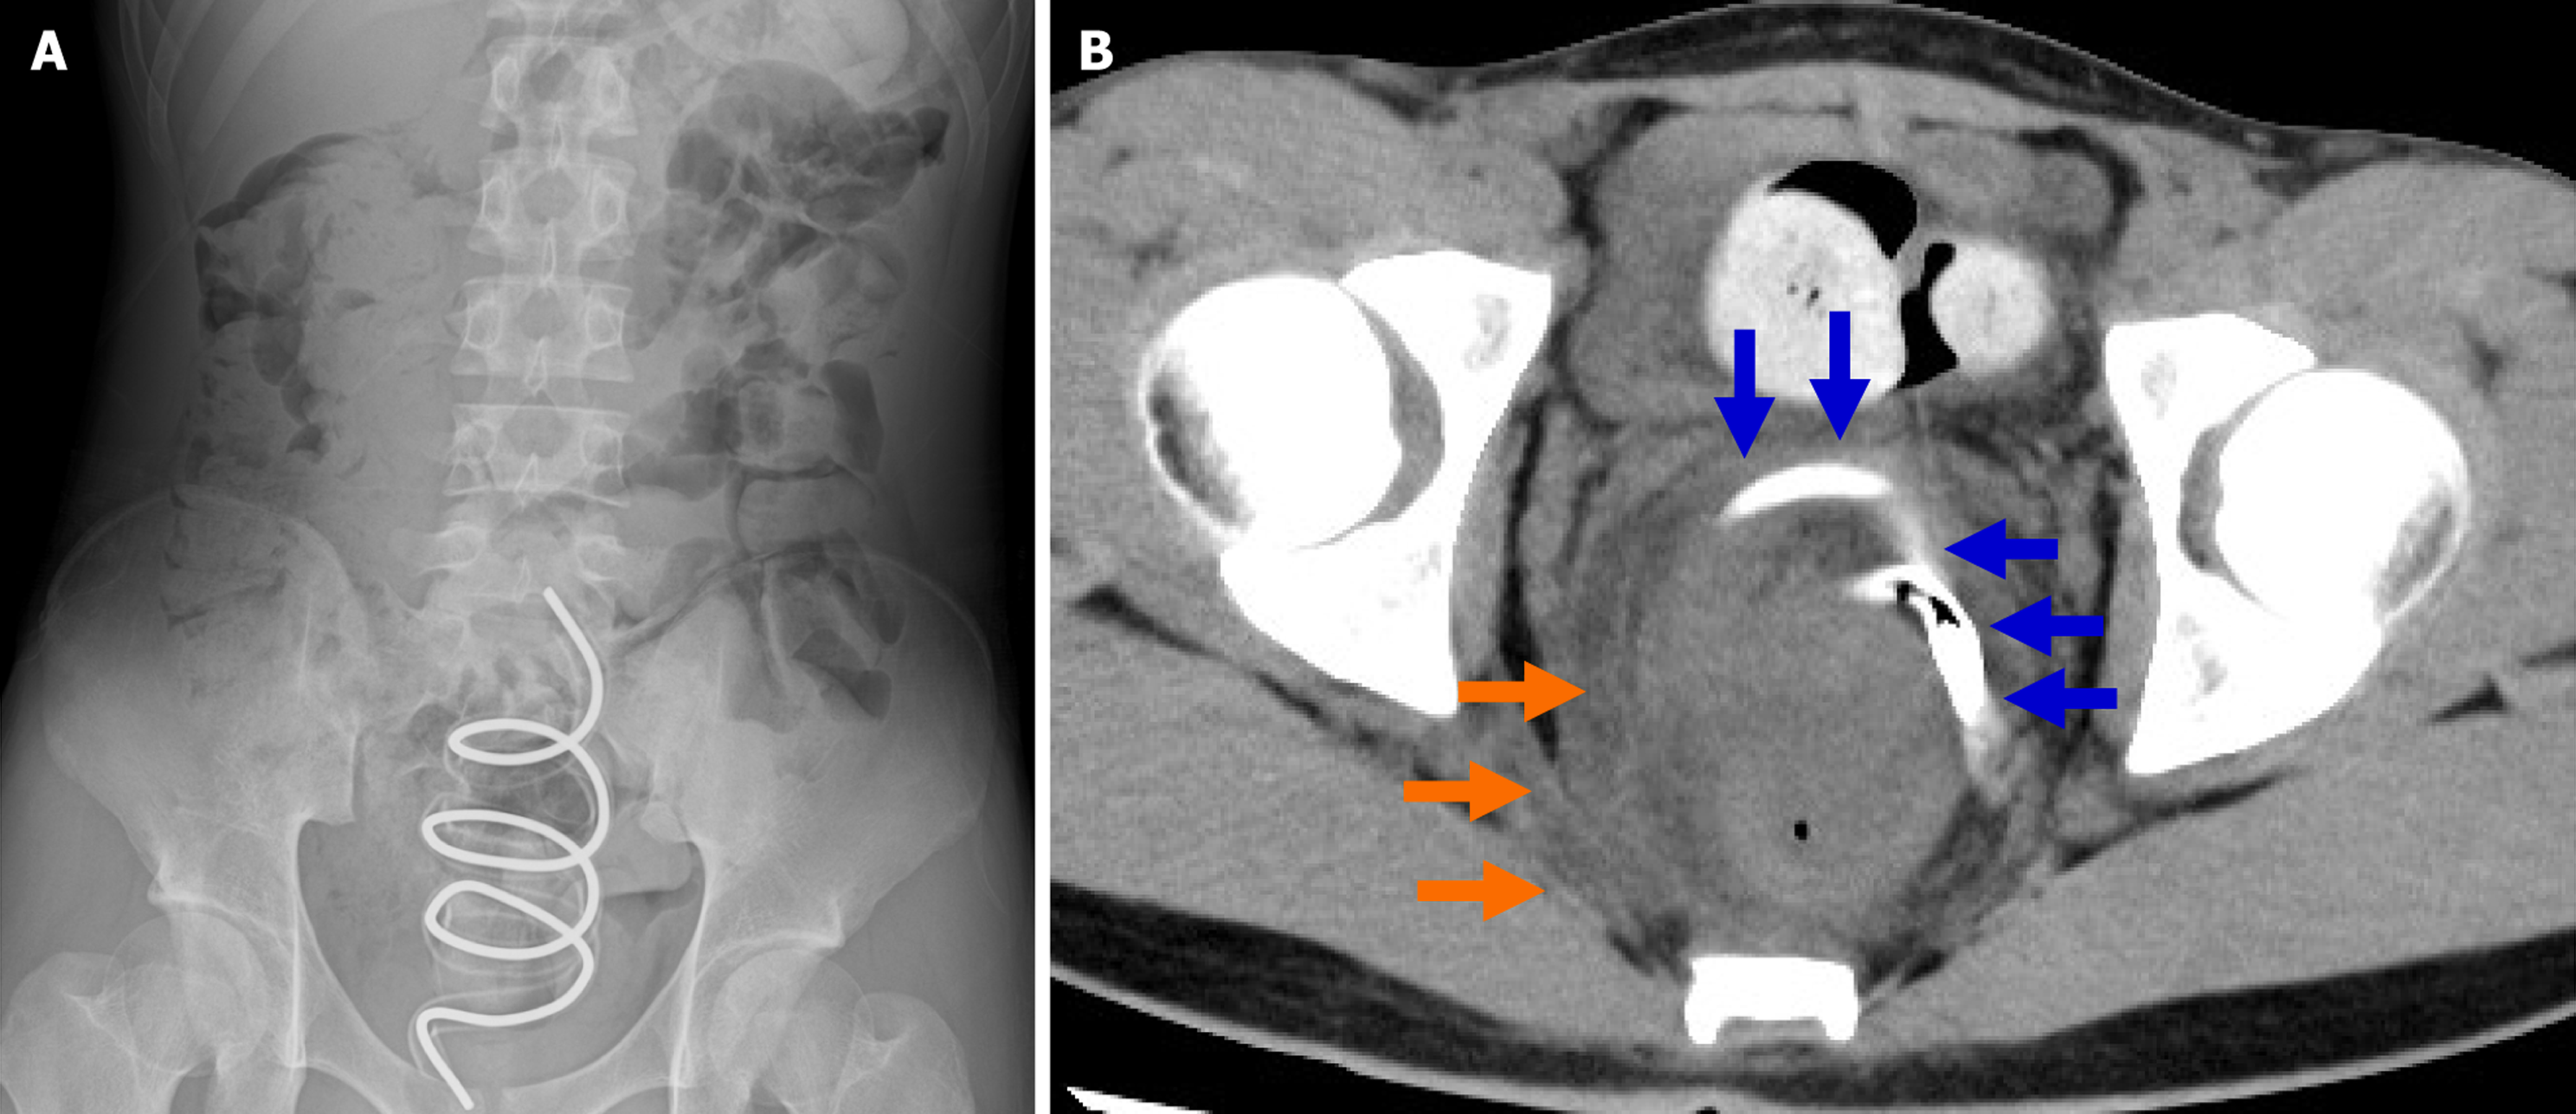

Supine abdominal radiography showed a low-radiolucent spiral-shaped foreign body measuring 17.5 cm long and 6.3 cm wide in the pelvic cavity, along with gas and a large amount of fecal material in the colon (Figure 1A). Plain abdominal computed tomography (CT) revealed the presence of a foreign body in the rectum (blue arrows), with edema of the rectal wall and increased density of the surrounding fat tissue (orange arrows). In addition, marked fecal retention was obs

The suspected diagnosis was an RFB caused by a smartphone stand, resulting in perforative peritonitis.